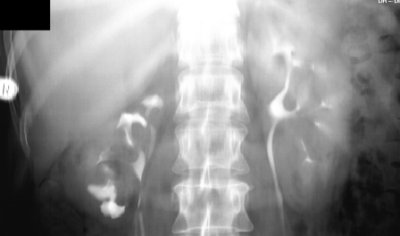

Das Ausscheidungsurogramm bei einer Patientin mit rezidivierenden Harnwegsinfekten mit Dysurie und immer wieder auftretenden Flankenschmerzen rechts gab Verdacht auf eine doppelt angelegte Niere rechts mit kleinem separaten Organ (Abbildung 6).

Unter Berücksichtigung der immer wieder aufgetretenen Harnwegsinfekte wurde die dysplastische kleine Niere entfernt (Abbildung 5)